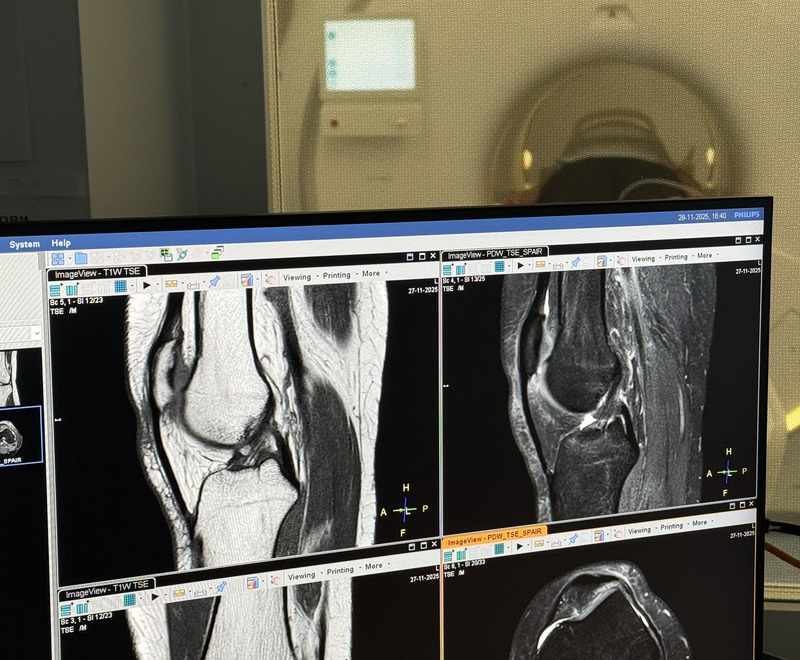

КТ коленного сустава — это высокоточный и неинвазивный метод диагностики, основанный на рентгеновском сканировании. Исследование позволяет получить послойные изображения костных и мягких тканей коленного сустава, а также прилегающих к нему структур (связок, сухожилий и др.). Компьютерная томография коленного сустава визуализирует точную анатомию, патологические изменения и травмы сустава, что помогает врачу поставить диагноз, составить план лечения и контролировать его результаты.